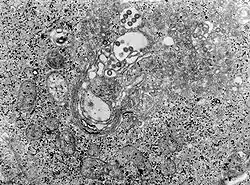

| TEM micrograph of tissue infected with Rift Valley fever virus | |